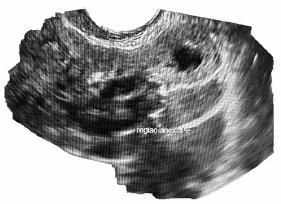

C.V.R.S., 36 anos, G VII P VI (6N) A0, IG cr: 6 semanas,deu entrada no PSGO com sangramento vaginal há cerca de 1 semana. Sem ultrassom prévio. Ao exame físico: especular: colo uterino sem lesões, mínima quantidade de sangue vermelho escuro em fórnice posterior. TV (toque vaginal) bimanual: colo impérvio, grosso, posterior. Ausência de dor à mobilização do colo uterino. Abdome: DB negativo, dor leve à palpação profunda de hipogástrio. Submetida à ultrassonografia transvaginal (imagens a seguir: figuras 1, 2, 3, 4) e beta HCG quantitativo: 9 000 UI/mL. Resultado de beta HCG 24h antes: 7 000 UI/mL.

Figura 2 (região anexial E; ovário E sem alterações)